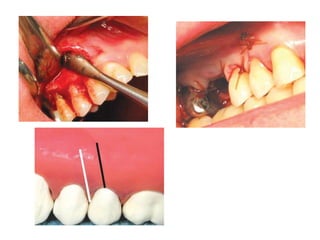

Plastic Closure of Oroantral Fistula

Cause

During extraction of an impacted maxillary

canine

-Excessive bone removal

-Failure to locate the tooth

Prevention

-Proper preoperative radiographic evaluation

-Proper bone removal

-Controlled force